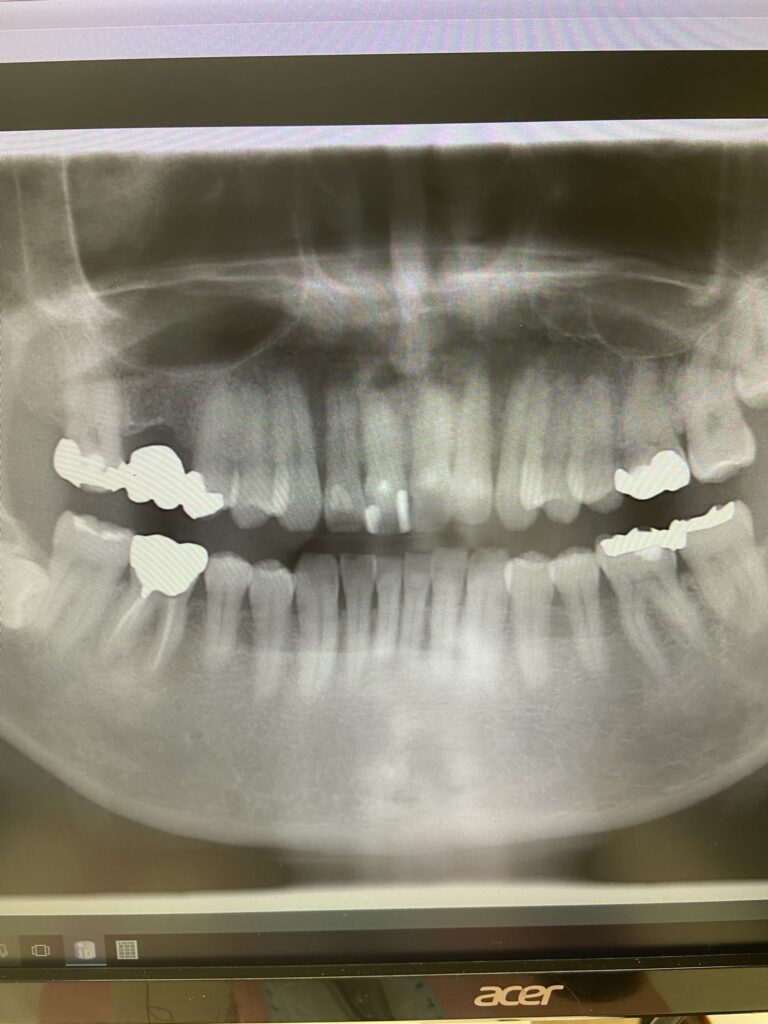

そこでレントゲンを撮影したところ、虫歯も、歯の根の先に膿がたまる「根尖病巣」も見つかりません。

- レントゲン撮影:虫歯や根尖病巣の有無を確認